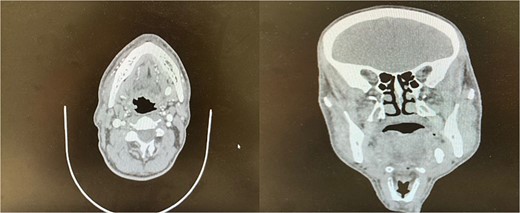

The accuracy of navigation was periodically verified by referencing stable bony landmarks, such as the mental foramen and mandibular condyles, with the navigation probe. Realignment was conducted as needed to ensure consistent anatomical mapping and precise localization of the submandibular stone (Fig. 2). After surface registration, a 1 cm mucosal incision was made intraorally at the nearest point indicated by the navigation pointer, parallel to the anticipated course of the Wharton duct. Blunt dissection was performed to expose the duct, with navigation toward the stone guided by the system. Great care was taken to protect the lingual nerve throughout the procedure. The depth of dissection was gradually advanced by periodically verifying the position with the navigation pointer probe (Fiagon) to maintain precision. During dissection, the stone was accurately located within the gland parenchyma using real-time visualization, and it became palpable, distinguished by its unique color and texture (Fig. 3). The stone was fragmented and removed in pieces because it was fixed (Fig. 4). The surgical field was flushed with saline to remove any residual stone debris, and the incision was closed with 4/0 Vicryl, which is an absorbable suture.

Fragments of the submandibular gland stone extracted during surgery.